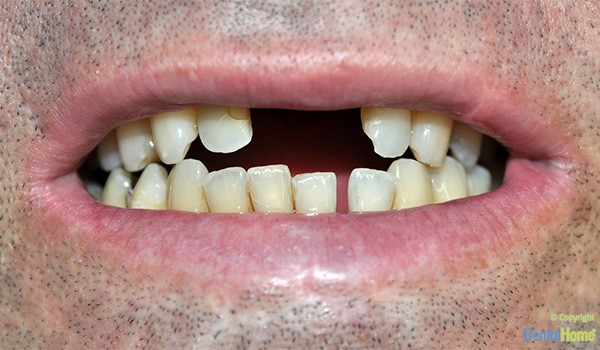

Galería de imágenes de coronas y puentes fijos